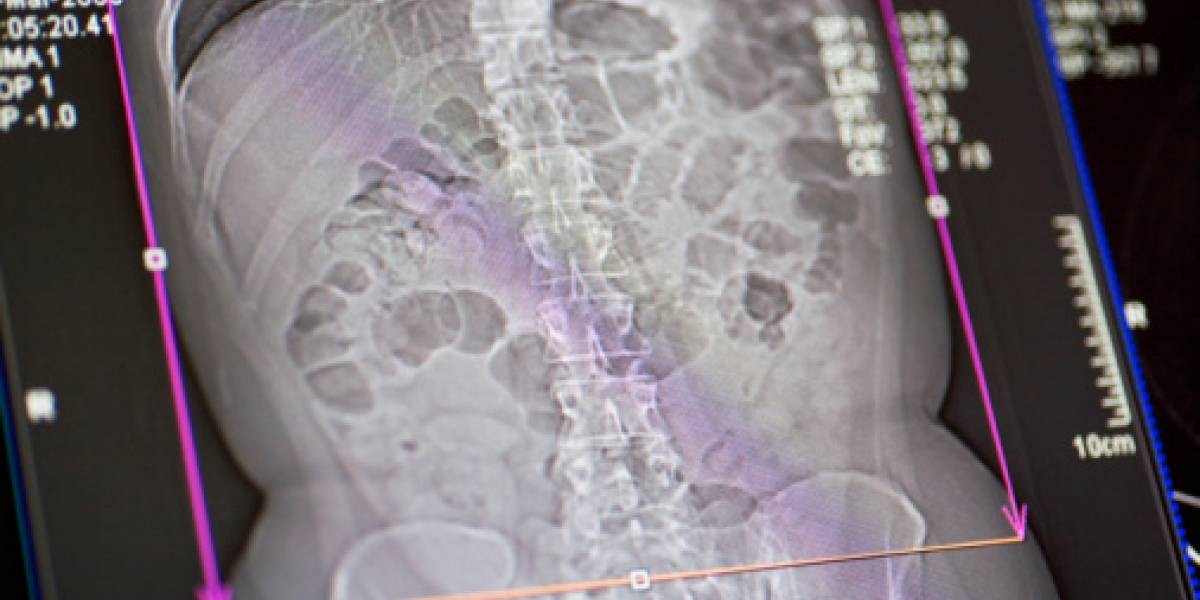

Tras efectuarle una tomografía computarizada a la adolescente, se encontró "una masa bien definida", indicándose que esta presentaba elementos de tejido adiposo y secciones de formaciones semejantes a huesos.

Luego de los análisis de rigor se determinó que tenía fetus in fetu, realizándose posteriormente una operación para extraerle el "gemelo". Allí, se halló un cuerpo que medía 30×16×10 centímetros. Este tenía además pelos y "múltiples dientes".